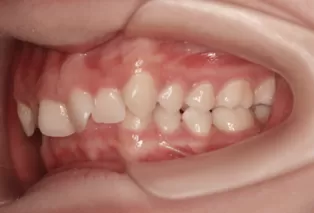

Intraoral photos